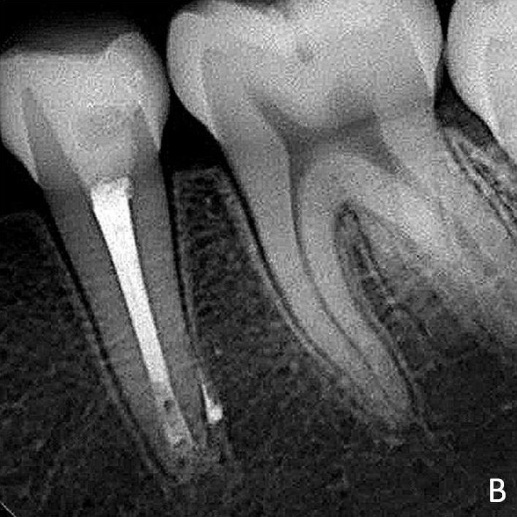

During the first appointment, the provisional material was removed, and the coronary access was refined with an inactive tip multilaminated bur (Endo Z, Angelus) (Figure 1B). This was followed by instrumentation of the cervical and middle thirds, after a calcium hydroxide associated with saline solution was used as intracanal dressing.

Figure 1B. Clinical aspects after refinement of the coronary access.